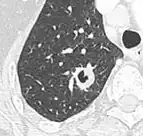

- Pleural retraction is far more common in cancers.[9] It is the pulling of visceral pleura towards the nodule.[9]

-

Nodule with pleural retraction.[9] -

In this case, pleural retraction is seen as a triangular fat component.[9]